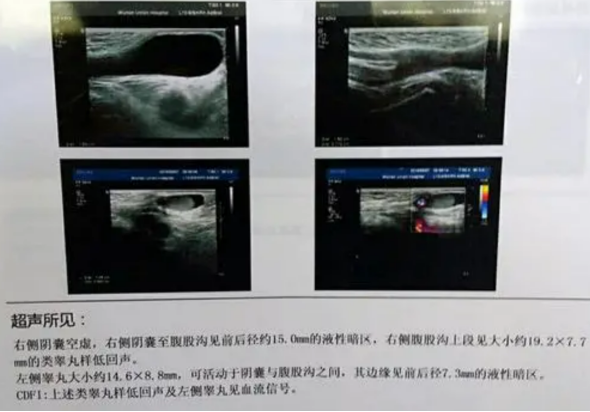

根据体格检查可分为睾丸下降不全、睾丸缺如、睾丸异位。在胎儿发育过程中,睾丸未下降入阴囊而停留于异位,大约80%隐睾位于腹股沟内环口下方,但未下降至同侧阴囊内;20%位于腹腔内,可停留在肾下极至内环口之间的任何位置。

超声表现为:阴囊内未探及睾丸回声;可探及的隐睾呈类圆形,体积小、回声低。